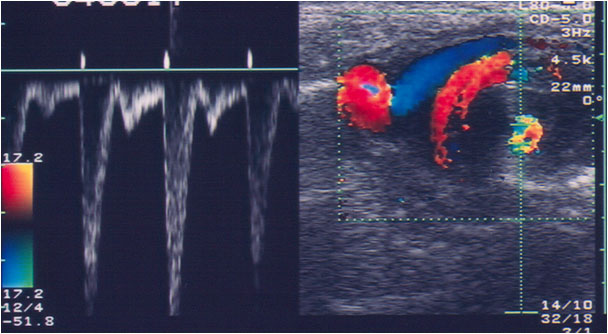

Signo de vólvulo de intestino delgado en pacientes pediátricos, en la ecografía doppler. El vólvulo provoca un plegamiento de la vena mesentérica superior y el mesenterio alrededor de la arteria mesentérica superior. En doppler se ve una imagen de remolino en el sentido de las agujas del reloj con el movimiento caudal del transductor en el plano axial.

La imagen de la izquierda muestra el espectro del doppler en el que se observa un patrón de alta velocidad. A la derecha, la imagen en modo B corresponde al arremolinamiento de los vasos mesentéricos.

Artículo de referencia: Shimanuki, Y y cols. Clockwise whirpool sign at color Doppler US: an objective and definite sign of midgut volvulus. Radiology 1996; 199: 261-264. Puedes consultar el abstract en http://pubs.rsna.org/doi/pdf/10.1148/radiology.199.1.8633156.